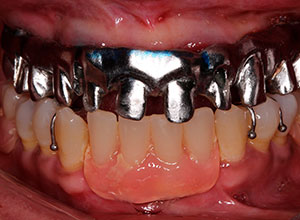

La prótesis dental híbrida es una estructura fija atornillada sobre implantes dentales que tiene como objetivo reponer las piezas dentales y tejidos blandos -encía- perdidos.

Dicha sensación se debe fundamentalmente a que es fija y no lleva paladar. Por ello, aporta gran estética, seguridad y comodidad a quien la lleva.

La prótesis dental híbrida consta de una estructura de metal recubierta de varias capas de porcelana blanca y rosa que dan la estética de los dientes y de la encía.

Dicha estructura se atornilla sobre los implantes que se han colocado previamente en el hueso mediante la cirugía.

Esto se hace mediante unos tornillos intermedios que fijan toda la estructura y sellan el espacio entre la prótesis y los implantes.

Por último, la entrada de estos tornillos a través de la prótesis se sella mediante el uso de teflón y resina, como si se estuviera realizando una obturación o empaste dental.